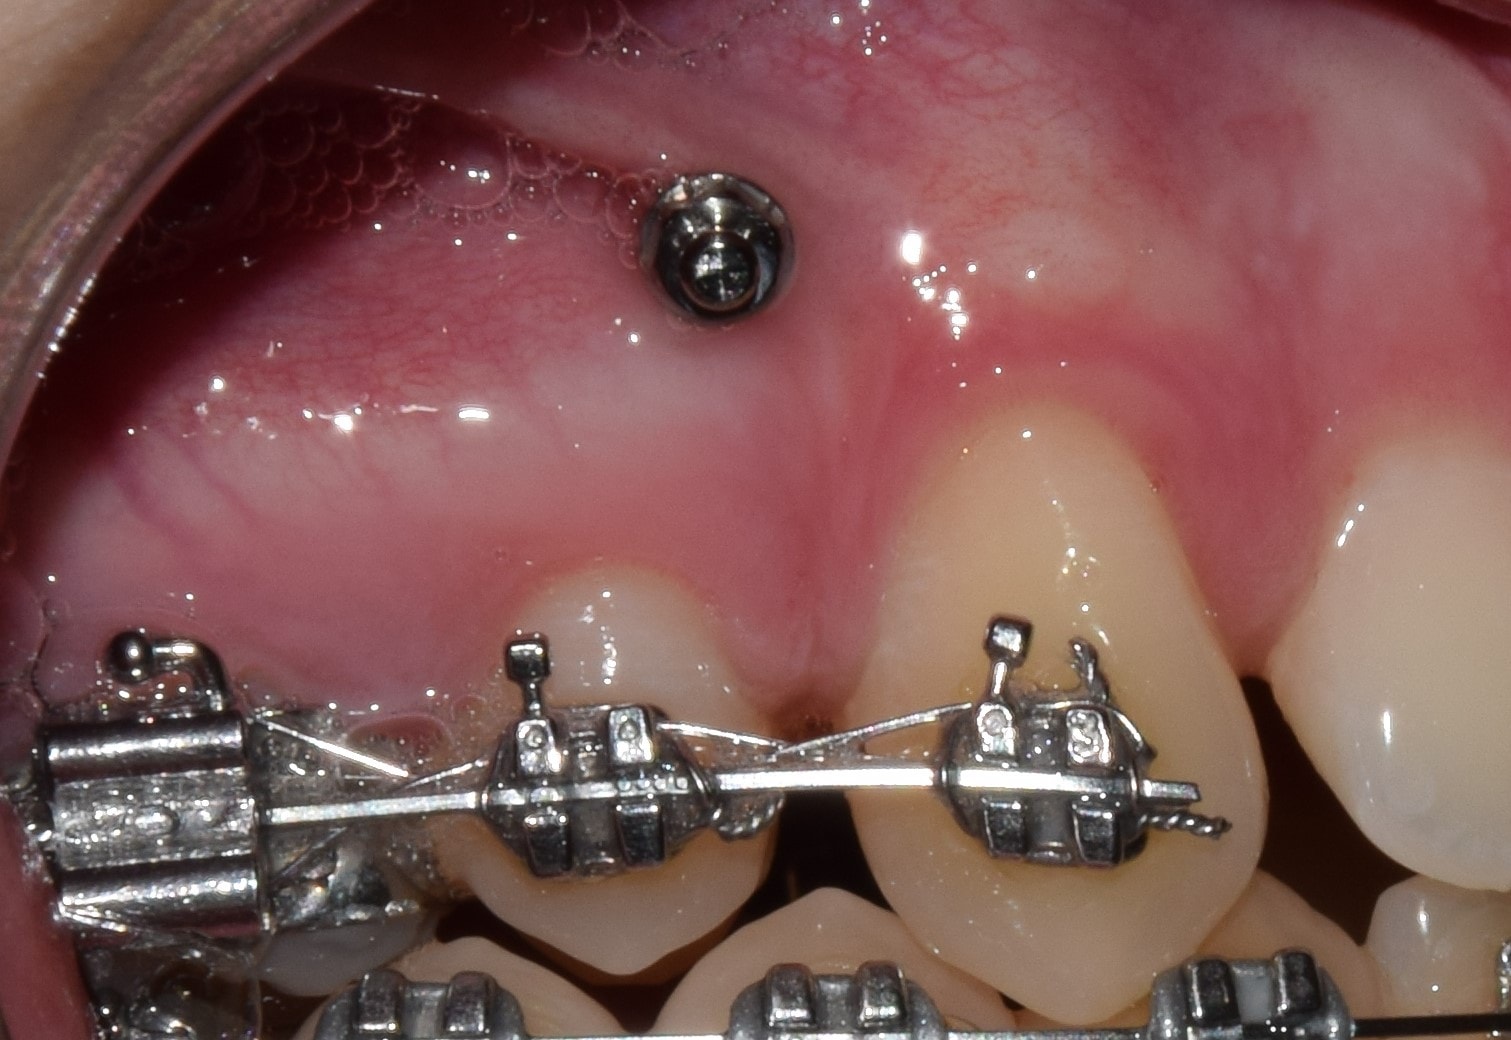

Fogszabályozási miniimplantátum

A modern fogszabályozó kezelések alappillérei a fogszabályozási miniimplantátumok. Óriási előnyökkel jár használatuk, és a kezelések sikerességét hihetetlen mértékben megnövelik. Miniimplantátumok segítségével a korábban csak műtéttel, foghúzással kezelhető pácienseket egyszerű fogszabályozással is tökéletesen kezelni tudjuk! Az önligírozó fogszabályozó rendszerek és miniimplantátumok kombinált használata talán a legsikeresebb technikát jelenti jelenleg. Nagyon minimális helyi érzéstelenítésben történik behelyezésük, mely nagyjából 20-40 másodpercet vesz igénybe! Az injekciót leszámítva teljesen fájdalommentes beavatkozás! A fogszabályozási miniimplantátumok a fogászati implantátumokkal szemben nem kerülnek szoros kapcsolatba a környező szövetekkel, ezáltal későbbi eltávolításuk igazán egyszerű, érzéstelenítő sem szükséges hozzá. Technika- és szájhigiéné érzékeny rendszerről beszélünk. Nem megfelelő fogmosás következményeként a minicsavarok meglazulhatnak, kieshetnek.

Behelyezési területük szerint három fő csoportot különböztetünk meg:

1. A gyökerek közé helyezett miniimplantátumok

Ezeket a miniimplantátumokat a fogak gyökerére merőlegesen helyezzük be, a gyökerek közé. Pontos helyzetüket előzetes kisröntgen alapján határozzuk meg. Ezekkel végezzük a foghiányok zárását, bizonyos fogak pozícióban tartását, elülső fogak felfelé/lefelé mozgatását stb.

2. A gyökereken kívül helyezett miniimplantátumok

Egyre népszerűbb technika, melynek során a minicsavarokat vagy a felső őrlőfogak melletti csonttaréjba (crista infrazygomatica), vagy az alsó őrlőfogak melletti csonttaréjba tekerjük. Előnye, hogy a foggyökereken kívüli területen rögzül a csavar, így nem akadályozza a fogak mozgatását. Segítségével teljes alsó/felső fogív előre/hátra mozgatás is végezhető.

3. A szájpadba helyezett miniimplantátumok (szintén a gyökereken kívül)

Nagy sikerrel alkalmazott, biztos, kiváló csontminőségű behelyezési terület a szájpad. A szájpad középvonalába, vagy enyhén mellé helyezzük be a minicsavarokat, amikkel a felső fogív hátra/előrevitele, és felfelé mozgatása is sikerrel végezhető. Nem kell tehát félni a miniimplantátumoktól, minden esetben nagymértékben segíthetnek minket a tökéletes végeredmény elérésében. Sikerességi rátájuk 95% körül mozog! Akkor is ismertetem használatukat, ha nem biztos, hogy szükség lesz rájuk, hiszen biztosra megyünk és tökéletes mosolyt és harapást szeretnénk.